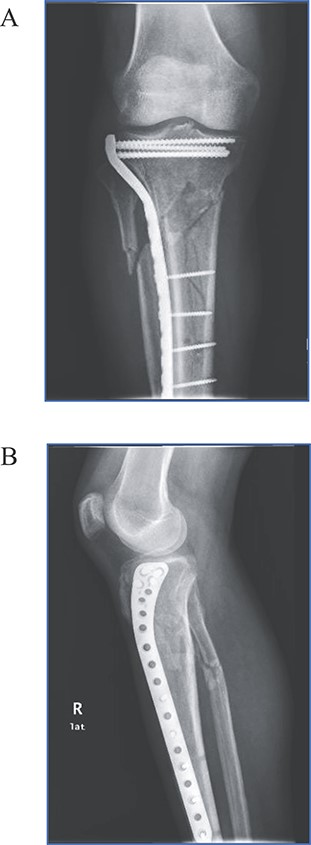

A 39-year-old male pedestrian was injured in a motor vehicle accident and then transferred to our emergency room on the same day of injury. Patient was stable after the accident and medical history was noncontributory. Physical examination of the right leg demonstrated considerable soft-tissue swelling around the knee and proximal tibia deformity and no signs of neurovascular injury. Imaging revealed a Schatzker type VI tibial plateau fracture (Fig. 1). Computer tomography angiography revealed no vascular damage. The leg was immobilized with a splint, adequate analgesia was prescribed and the patient was admitted to ward.

Radiographic views demonstrating a complex proximal tibia fracture of the right leg.